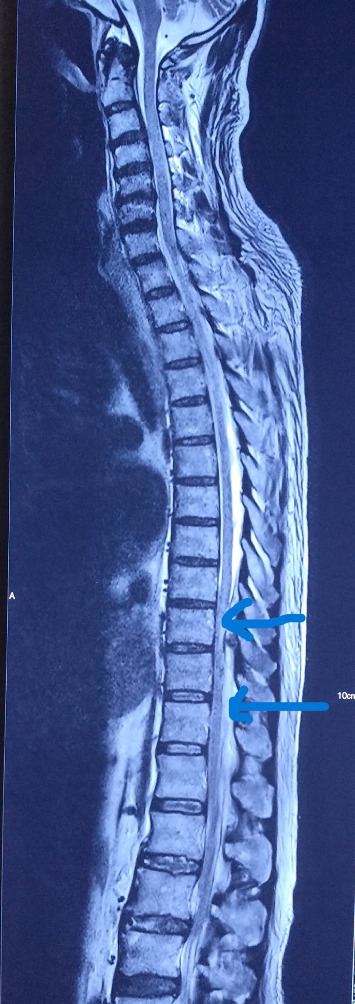

Background: Staphylococcal infection is a common bacterial disease with common clinical features. Untreated infection, especially in immunosenescence cases, can affect other organs. This can lead to multiorgan dysfunction and cause increased morbidity and mortality. Unlike commonly presented features of pneumonia, dissemination of infection can pose diagnostic and therapeutic enigma. Therefore, any such presentation in common clinical practice can yield a conundrum of diagnoses. Case Report: A 69-year-old elderly male presented to the Emergency Department with acute onset encephalopathy. Historically, cues were limited, and evaluation was negated for acute cerebrovascular event or seizure. Laboratory findings were suggestive of a severe sepsis. While clinical medicine workup and diagnostic dilemma were ongoing, possible sources of the sepsis were thoroughly sought including range of infectious causes. This patient's presentation was one of its kind: staphylococcal bacteremia seeding to cause pneumonia and unusual epidural abscess in due course of illness. Conclusion: The health outcome of the critically ill especially elderly patients depends mostly on the importance of clinical medicine to address the diagnostic enigma and virtue of supportive care delivered. Staphylococcus aureus infections are capable of developing distant infectious foci, as highlighted in this case, and that the clinician should be alert to this possibility. This particular case firmly posits an admonition for clinicians and the importance of clinical medicine for critical reasoning to improve the patient outcome.